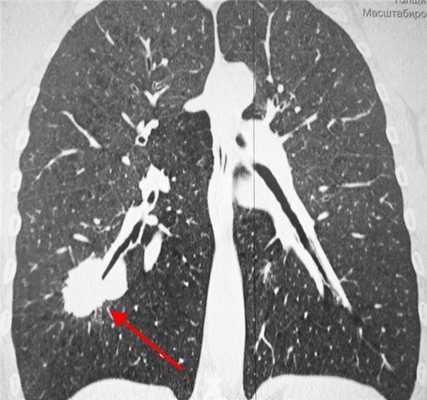

Метастазы в легких на КТ

Гематогенные метастатические узлы в легких на КТ имеют довольно четко очерченные и ровные контуры. Нечеткие, расплывчатые или лучистые контуры наблюдаются в том случае, если есть инвазивный рост в окружающую легочную ткань. Локализуются преимущественно в нижних, периферических отделах легких, хаотично, без очевидной связи с бронхами и крупными легочными сосудами.

Вторичные узлы гематогенного характера чаще всего имеют ровные края, четкие контуры и однородную структуру. Возможны изменения структуры опухоли вследствие кровоизлияния в паренхиму, обызвествлений, некроза центральной части узла, а также рубцов. Края узла могут стать нечеткими, расплывчатыми, если опухоль провоцирует отек легочной паренхимы, либо «лучистыми», если имеет место опухолевый лимфангиит.

Чаще всего метастазы выглядят как множественные очаги. Одиночные вторичные узлы крайне редки и встречаются меньше чем в 5% случаев. Чем больше узлов выявлено, тем выше вероятность их метастатической природы. Одиночный метастаз нужно дифференцировать с первичным раком, для этого обычно требуется тканевое исследование после оперативного вмешательства или биопсии.

Гематогенные метастазы наиболее часто локализуются в периферических отделах легких, вдали от крупных сосудисто-бронхиальных пучков, вблизи плевральной оболочки. При множественных поражениях гематогенного характера наблюдается тенденция к увеличению количества очагов в направлении «сверху-вниз». Чаще гематогенные метастазы расположены хаотично, вне четкой связи с бронхами и видимыми легочными сосудами. Практически не бывает такого, чтобы гематогенные вторичные узлы находились только с одной стороны, или занимали только одну долю или сегмент. При наличии такого распределения в первую очередь нужно думать о туберкулезе (верхние доли), множественных абсцессах и т. д.